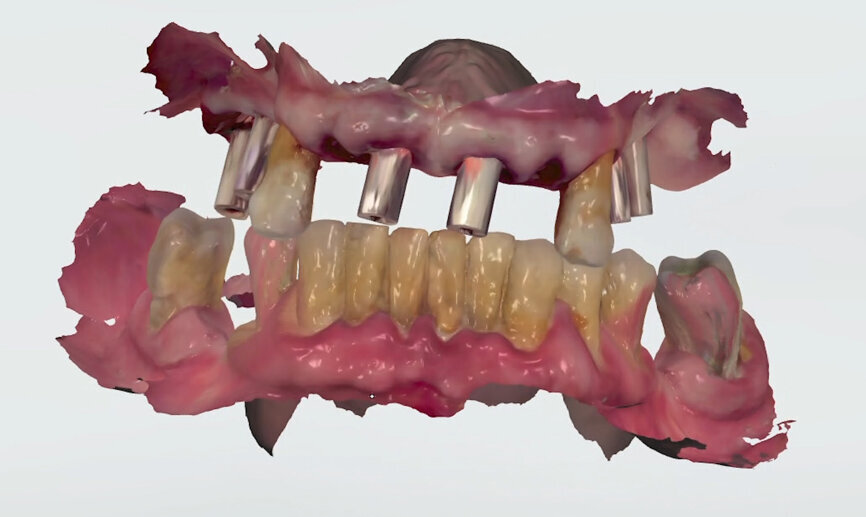

On receipt of the scan body file (File 2), the laboratory imported it into 3Shape’s Dental System and created a virtual model, matching the virtual SRA scan bodies from Straumann’s original library with the intra-oral SRA scan bodies (Figs. 13 & 14). A working file was created for designing the temporary prosthetic emergence profile for the SRA.

To perform the design of the temporary full-arch prosthesis and maintain (or modify) the vertical dimension of occlusion and occlusion, the patient’s pre-preparation study model scan file (File 1) was imported as a pre-preparation scan (blue) and merged with the implant file scan (File 2), using the preserved teeth present on both scans. The software allowed us to mark the same points on the preserved teeth on both files, the study model scan and the implant scan (both contained the preserved teeth). Thus, the laboratory was able to work on a single file containing both Files 1 and 2, merged by means of the preserved teeth. Designing the temporary prosthesis is an easy task using the image of the patient’s own teeth as a mock to be copied (Fig. 15). Any design modification can easily be done (Figs. 16 & 17).